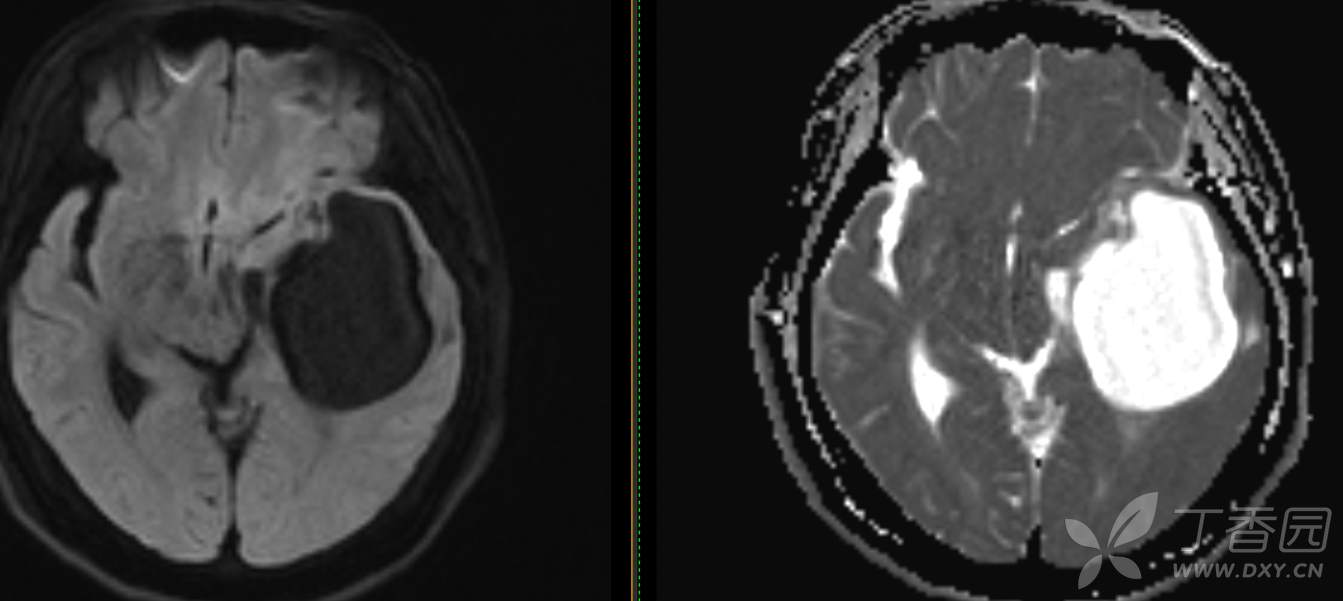

现病史: 【患者1月余前无明显诱因出现记忆力减退,易忘记事情,表现为忘记说过的话、易忘 事、理解力及计算力均尚可、阅读无受限、无性格脾气改变,无头痛头晕、无恶心呕吐、无视物模糊,无言语不利,无幻觉妄想,当时未重视未就诊。1月内记忆力减退进行性加重,对刚做过的事情即遗忘,计算力下降,日常生活尚能自理。遂至我院门诊就诊,查“颅脑CT平扫:左侧基底节-颞叶区低密度占位,建议进一步增强 MRI检查。

患者既往子宫内膜癌手术史;高血压病史3年